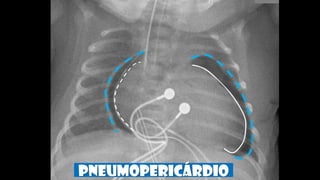

PNEUMOPERICÁRDIO

Sinal do diafragma contínuo